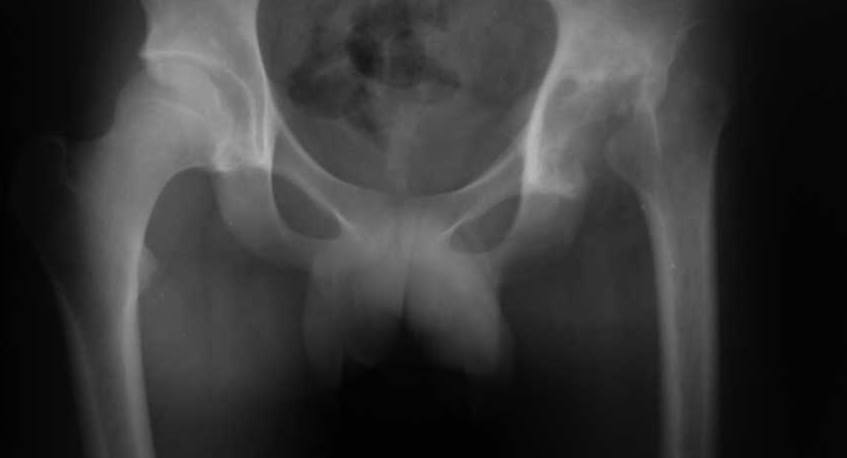

Ув. коллеги. пациент 19 лет, 4 мес назад перене гнойный коксит с затеками и т.д, 3 мес назад - резекция головки, санирование очага. В настоящее время кровь спокойная, СРБ - отр, рана зажила первично. Свищей нет и не было, т-ра в N. В какие сроки, по вашему мнению, целесообразно выполнить эндопротезирование, какие критерии? С уважением, Максим Агалаков, Е-бург.

Выполнять эндопротезирование Вашему пациенту, с моей точки зрения, категорически нельзя, так как очень высок риск развития нагноения в области имплантата. Никакие хорошие показатели крови здесь нипричем. Больному показано проведение комплекса ЛФК для укрепления мышц бедра, ягодиц, спины и брюшного пресса для лучшего функционирования уже созданного в ходе выполненной резекционной секвестрнекрэктомии головки бедренной кости опорного неоартроза. По рентгенограмме стояние проксимального отдела бедренной кости можно считать удовлетворительным. С методикой ЛФК по Маловичко для формирования опорного неоартроза с примерами лечения больных с данной патологией можете ознакомиться на моем сайте www. Malovichko. ru